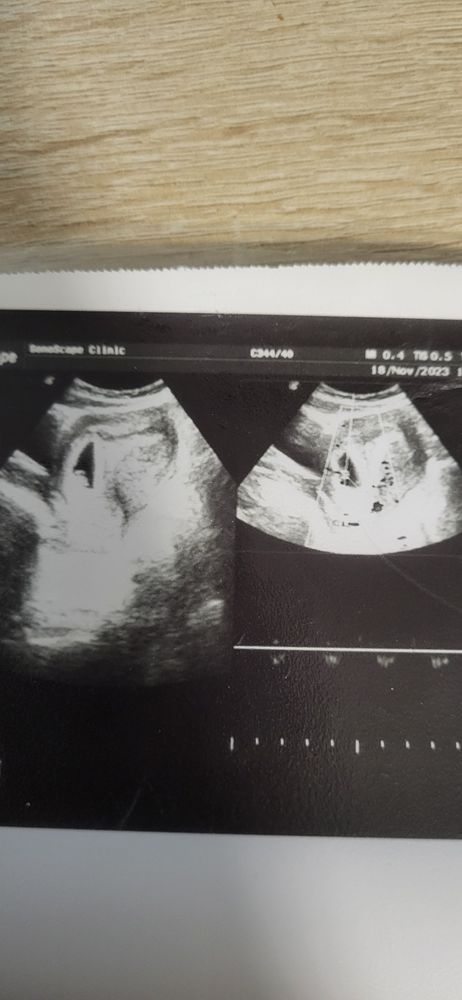

6.5 недель беременности, узи.

Сегодня ходила искать свою креветочку к своему любимому узисту. Последний раз делали трансвагинально 7.11 в больнице, ставили 4-5 недель. Думала мой узист тоже будет тем же способом смотреть, а он сказал, что нет, срок уже хороший, видно через живот будет и нечего лишний раз туда ползать. Посмотрели через живот. Нашли мою креветочку, срок 6.5 по узи) Сердцебиение показал на экране))) Это так мило. Сказал нормальная беременность, здоровая, хорошо закрепилась лялечка. Ни отслоек, ни гематом не нашёл. Обнаружил кисту в ля, сказал ничего с ней делать не надо, рассосётся. Вот думаю, недельку подожду и пойду вставать на учёт. Давайте погадаем по месту прикрепления, мальчик/девочка?)